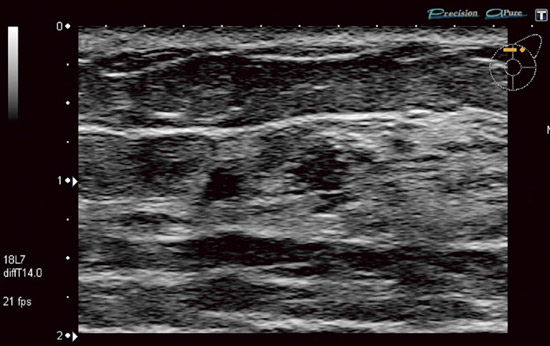

TOSHIBA PLE-705S型 リニア式電子スキャンプローブ エコー 超音波診断装置 東芝の詳細情報

カテゴリビューティー、ヘルスケア救急、衛生用品その他状態傷や汚れあり(詳細)■商品名:PLE-705S型 リニア式電子スキャンプローブ

使用による傷などが見受けられますので、詳しくは画像を参考にしてください。